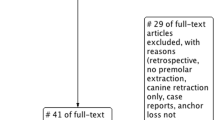

Two hundred sixty MIs (209 in maxilla, 51 in mandible) were categorized into success (n = 229) and failure (n = 31) groups. Distances from MI to the most adjacent tooth (DT) and to AC level (DC) were measured on periapical radiographs taken with the orthoradial projection technique. Appropriate statistical tests (chi-square, t test, logistic regression) were applied.

This retrospective study was approved by the Institutional Review Board ((ID#: OTO.RH.01). From a total of 293 MIs placed in 260 patients, right and left implants had been inserted in 33 patients. A separate comparison of the parameters analyzed in the study was conducted between right and left sides in these patients and revealed non-significant statistical differences. Accordingly, one of the MIs on either side was randomly selected for inclusion in the final sample of 260 MIs.